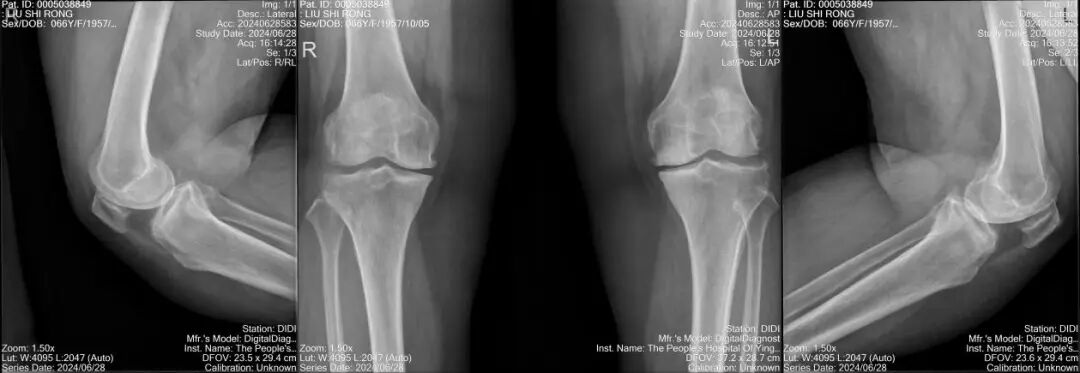

膝关节正侧位片X线片提示:双侧膝关节内侧的软骨完全磨损,内侧间隙狭窄,关节缘骨赘形成,初步诊断为双侧膝关节重度骨性关节炎。

郑奶奶伴有高血压、脑梗死、高尿酸血症等疾病和严重肥胖的特殊体质,术前联系心血管内科、神经内科、麻醉科及手术室等多学科进行会诊,而后经科室全体讨论,结合膝关节磁共振检查,认为郑奶奶是膝关节内侧单间室病变,外侧间室及髌股关节正常,膝关节韧带完整,关节活动范围基本正常,随行左侧膝关节内侧单髁置换术(UKA)治疗。